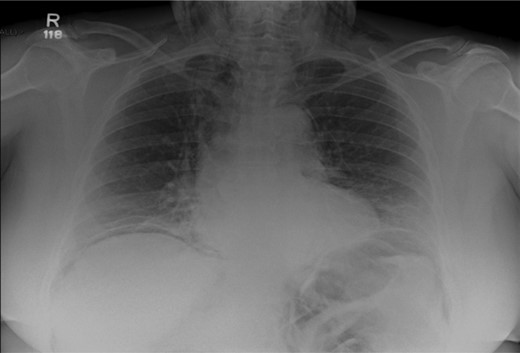

After her procedure she complained of swelling in her neck. This was not accompanied by shortness of breath, chest pain or abdominal pain. On examination, her oxygen saturation was 99% on room air, with normal respiratory and heart rate. Her respiratory examination was normal and her abdomen was soft and non-tender. She had marked crepitus over her clavicles, supraclavicular fossa and most of her neck. Her erect chest X-ray revealed air under both hemidiaphragms and significant pneumomediastinum (Fig. 1). A computed tomography (CT) scan of her chest, abdomen and pelvis was requested. This CT-scan revealed very extensive spreading of surgical emphysema in the retroperitoneum, extending into the mediastinum with small volumes of free intraperitoneal gas (Figs 2–4).

Chest X-ray illustrating pneumoperitonuem, pneumomediastinum and cervical emphysema.